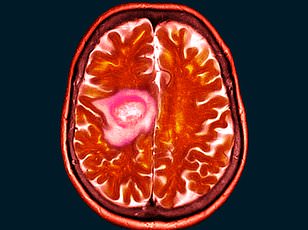

At the clinic, scans revealed a golf-ball-sized tumor pressing against her optic nerve—a rare condition known as a spheno-orbital meningioma. The news stunned her. "I was told immediately to stop using the contraceptive injection I'd relied on for 15 years," she said. The drug in question, medroxyprogesterone acetate (commonly sold as Depo-Provera), had been prescribed by her doctor for years to manage her fertility. Now, her neurologist linked its long-term use to the tumor's growth. "They said it was a risk I never knew about," she added, her voice trembling. "I used to encourage others to take it. I'd never imagine this could happen."

The surgery to remove 90% of the tumor took 10 hours, with surgeons painstakingly avoiding damage to her optic nerve. Shelley's left eye, once swollen and protruding, was now a stark reminder of the tumor's invasive nature. "It felt like something was pressing against my brain," she said, describing the pressure that had caused her vision to deteriorate. "If I'd delayed treatment by even a month, I could have lost my sight entirely." Despite the success of the operation, 10% of the tumor remains—a lingering threat that will require ongoing monitoring.